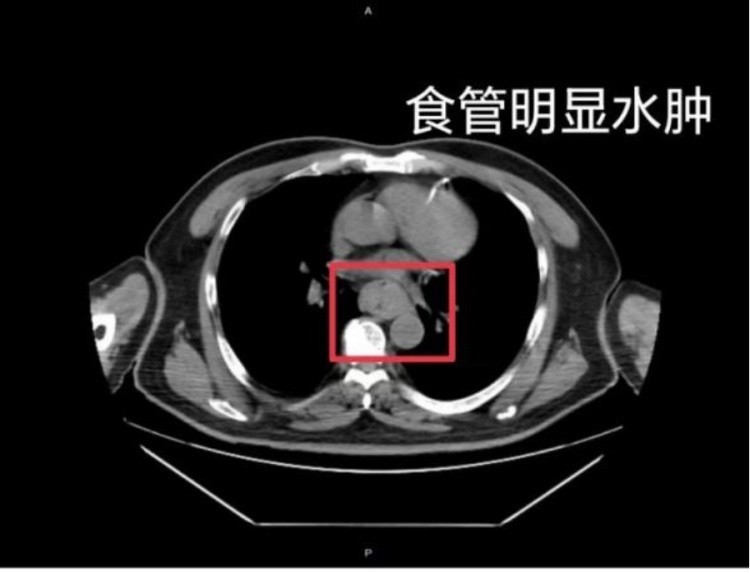

△图源:常州二院消化内科胃镜检查发现,蔡先生的食管黏膜出现大面积糜烂、剥脱,创面充血严重。经过抗炎、止血、保护消化道黏膜、输血等治疗,他的病情有所好转。这样的情况并非个例,同样在近日,福州一位网友分享了自己因吃了一碗很烫的福鼎肉片导致呕血,并查出食管水肿的经历。据网友回忆,“自己去厕所尝试呕吐时,直接呕出了血,一大口鲜血从嘴里喷出,总共吐了两次。”CT结果显示,他的食管全部出现水肿损伤。医生介绍,进食过烫的食物很容易损伤口腔、食管和胃黏膜,可能导致黏膜破损、炎症,甚至溃疡出血,从而引起胸腹部疼痛、烧心等症状。虽然消化道黏膜上皮有再生和修复功能,但长期反复刺激,可能引起黏膜慢性损伤,并增加食管炎和消化道溃疡以及癌变的风险。食管烫伤的症状有哪些?轻度食管烫伤可能并没有明显的感觉或症状,但随着烫伤程度逐渐加重,可能会出现以下症状:1.疼痛 :疼痛是食管烫伤最典型的症状。烫伤会损伤食管表皮组织,导致食管内部出现灼痛感或刺痛感。2.异物感 :会造成食管黏膜损伤,引发局部水肿、充血,使患者感到食管中有异物存在。3.吞咽困难 :会损伤食管软组织,导致患者吞咽时感到不适,进而引发吞咽困难。4.声音嘶哑 :会对喉咙黏膜形成损伤,造成咽喉部水肿,影响到声带。5.咯血或呕血 :若烫伤较严重,可能会引发食管破裂或血管出血,导致咯血或呕血。6.黑便 :食管出血可能随大便排出,血液被氧化后呈黑色,从而引起黑便。烫伤后该如何处理?家有幼儿,这些事要注意!该如何防止孩子误吞滚烫的食物?医生建议,父母在照顾孩子时一定要做到心中有数,对于滚烫的食物,要先确定好温度才能给孩子吃。可将食物放置在离孩子比较远的地方,禁止小月龄又比较调皮的孩子进入厨房。